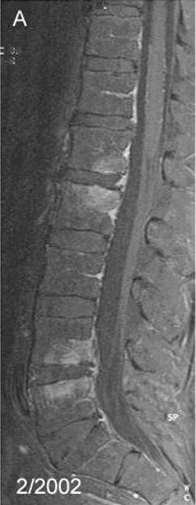

| Spondylitis due to Tropheryma whipplei. Contrast-enhanced, T1 weighted fat suppressed magnetic resonance imaging demonstrating contrast enhancing lesions of spondylitis in the first (L1) and second (L2) as well as fourth (L4) and fifth (L5) lumbar vertebra, sparing the intervertebral discs. | |